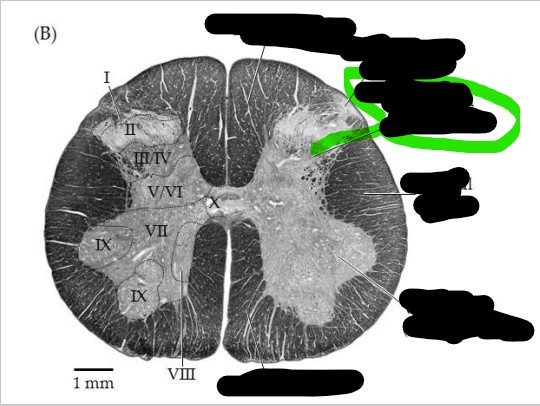

Spinal cord - dorsal horn

left and right posterior masses of gray matter; axons of sensory neurons and the cell bodies of interneurons located here